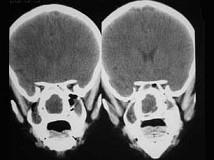

问题 女、14岁,渐进性鼻塞2年余,右眼肿痛数月,CT如图所示,应诊断为()

选项 A.筛骨骨肉瘤 B.筛骨骨纤维异常增殖症 C.筛骨软骨瘤 D.筛骨结核 E.筛骨骨化性纤维瘤

答案 E